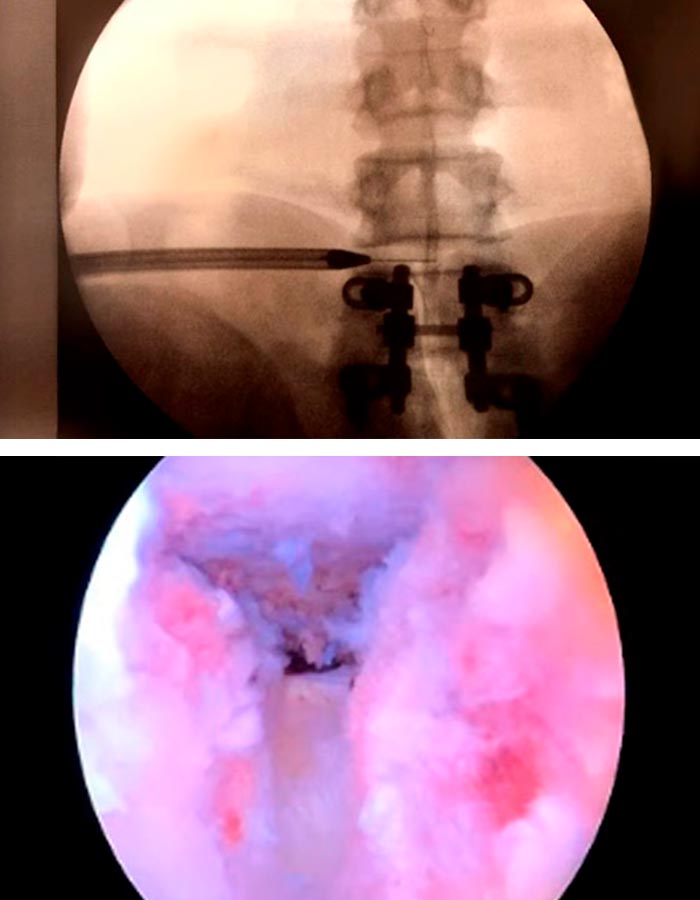

La cirugía mínimamente invasiva de endoscopia de avanzada de columna se lleva a cabo en unas dos horas a través de un portal de unos 3mm, situado en la parte posterior de la columna :

1. Se introduce una aguja guía que nos ayudará a introducir un dilatador para acceder a la zona de trabajo sin dañar ningún tipo de tejido.

2. Una vez localizado el nivel y visualizado el disco procedemos a extraer la hernia muy despacio para que no se desprendan nuevos trozos.

3. Se revisa bien la zona y se retira un nuevo trozo alojado detrás del primero.

4. Cuando ya se ha retirado toda la hernia debemos limpiar ambos lados de la vértebra para asegurarnos de que el canal está limpio y el tejido neurológico tiene el espacio correcto y está completamente liberado.

5. Por último, cauterizamos bien la zona que rodeaba al fragmento extraído.

6. Se realiza una infiltración con corticoides locales.